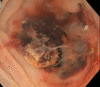

Unusual cause of colonic mucosal ulceration and gastrointestinal bleeding

Keywords: colorectal pathology; gastrointestinal bleeding.